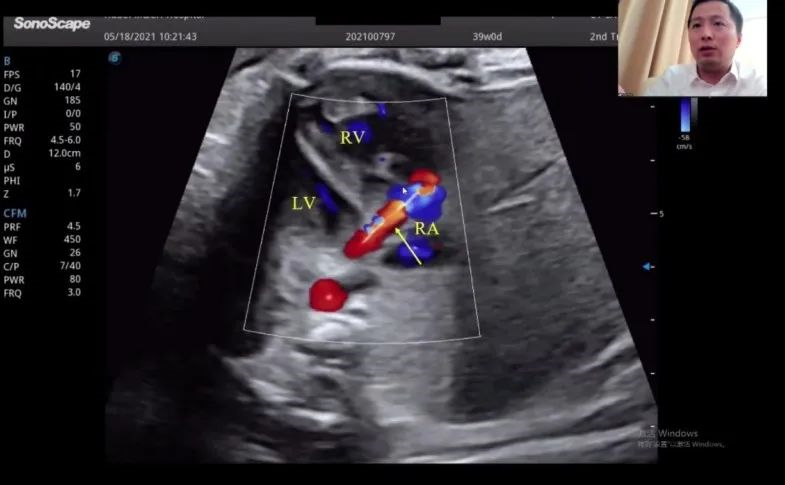

浙江大學醫(yī)學院附屬邵逸夫醫(yī)院的趙博文教授聚焦先天性心臟疾?。–HD)的產(chǎn)前診斷,通過特殊病例的展示講解,包括法洛四聯(lián)癥(TOF,一種常見的先天性心臟畸形)的時空關聯(lián)成像技術(Spatio-Temporal Image Correlation,STIC)、大動脈完全轉位(cTGA)和右心室雙出口(DORV)的圖像,前瞻性地提出智能胎心的應用場景。“胎心檢查人工智能的應用非常有價值,能夠縮短檢查時間,提高臨床的診療效率,”趙教授如是說。

湖北省婦幼保健院的趙勝教授在會上帶來了胎兒冠狀動脈瘺超聲診斷研究的分享。趙教授表示,冠狀動脈瘺在妊娠晚期可通過超聲檢查顯示出來,經(jīng)線圈栓塞或冠狀動脈瘺術后,進一步的臨床過程通常較為順利。